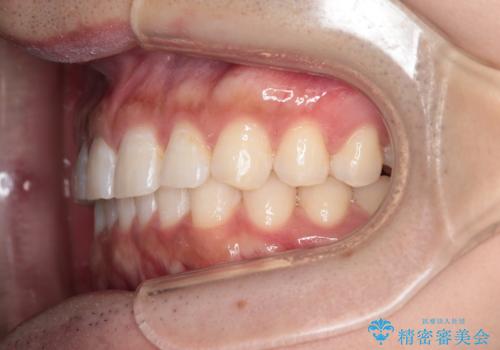

再矯正ということでがたつきはなくきれいに並んでいましたが、上下のアーチ(歯列弓)の大きさのバランスが悪く、結果的に後戻りの原因になってしまっていました。今回は下のアーチを小さくするためにIPRを行い、かみ合わせのバランスを治しながら前歯の隙間を閉じました。